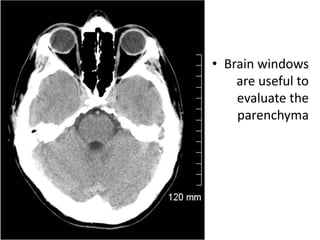

Read the information on the CT scan Do not get disoriented Hold the film in the proper orientation Follow the IV contrast filled Aorta as we descend caudally. CT scans of the mediastinum are reconstructed filmed and interpreted in an axial format. The mechanism is based on a quickly rotating narrow beam of x-rays directed towards a patient that produces signals that are processed by the machines software.